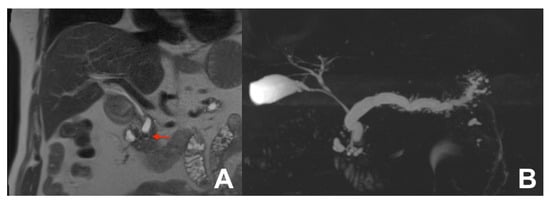

3. Pancreas